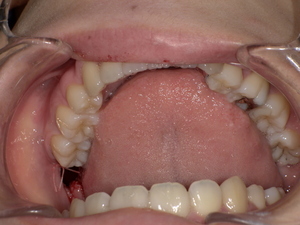

口の中に白っぽい「線状・網目状・斑点状」の病変が現れ、粘膜が硬く、時に痛みやヒリヒリ感、赤みを伴います。病変部がむずがゆい、物を噛むときに不快感がある、口内炎が繰り返すような感覚が現れる方も多いです。

口の中のどこにできる?(舌・頬・歯茎など)

-

頬の内側:もっとも一般的。

舌の横や裏:白斑が見られやすいです。

歯茎や唇の裏:発生することもあり、視認しづらいため注意が必要。

口蓋(上顎内側):稀に見られる部位。

口腔扁平苔癬の主な症状|痛み・赤み・白斑などの見分け方

初期症状と進行症状の違い

初期:細かい白い網目状、軽度のかゆみや違和感

中期〜進行期:白板形成、赤み、潰瘍、強い痛み、出血などが出ることもあります。